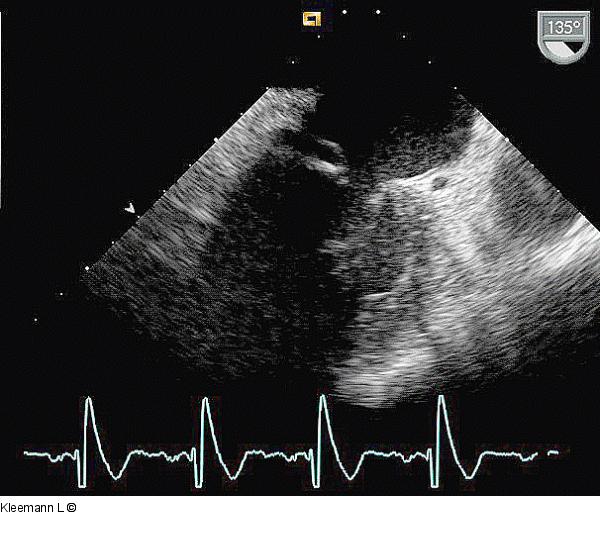

Abbildung 6: Echo TEE 24.09.: endlich zeigt sich die Vegetation rückläufig |

TEE 24.09.: endlich zeigt sich die Vegetation rückläufig |